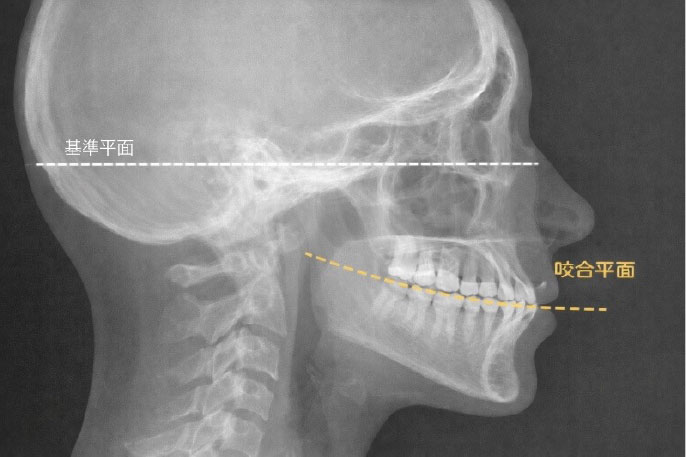

咬合平面とは?

歯が並んでる状態を面としてとらえると、咬合平面という考え方ができます。

これはレントゲンや模型(歯型)などで細かく分析できるのですが、各々の骨格にあわせて、また顎がどのように動いているかも考慮して、理想的な咬合平面が決まってきます。この理想的な咬合平面上に歯が並んでいると、良い咬み合わせといえると考えます。